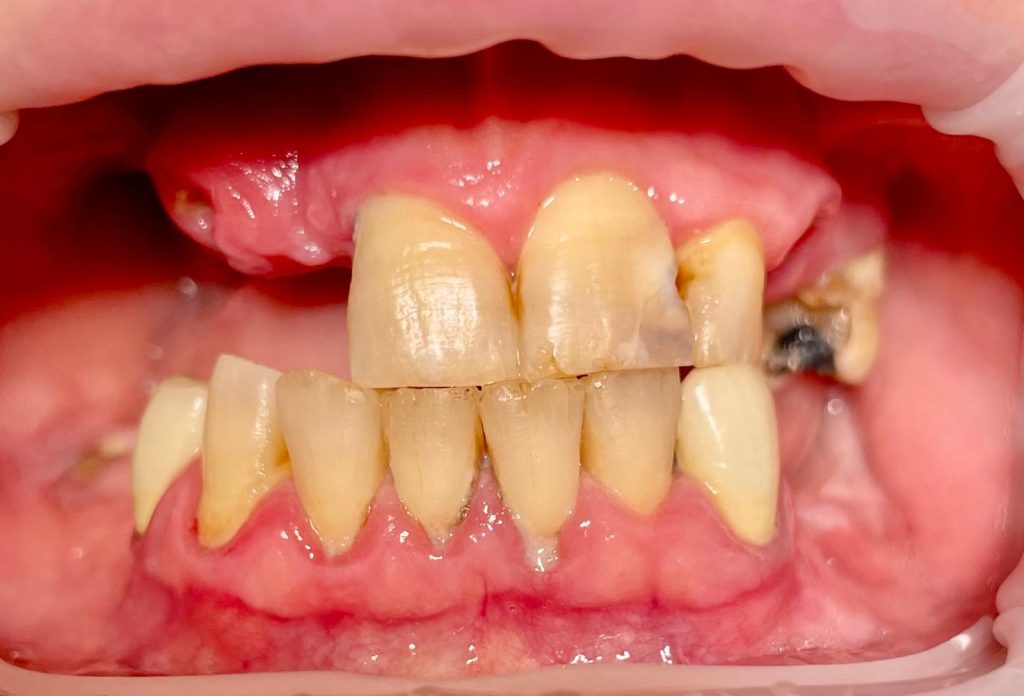

Questa settimana vi presento un caso di riabilitazione immediata dell’arcata superiore eseguita in chirurgia computer guidata con l’utilizzo di dime scomponibili.

L’intervento ha previsto l’estrazione degli elementi dentari, l’inserimento di 5 impianti nell’arcata superiore, il montaggio delle torrette provvisorie e la ribasatura del provvisorio nel cavo orale.